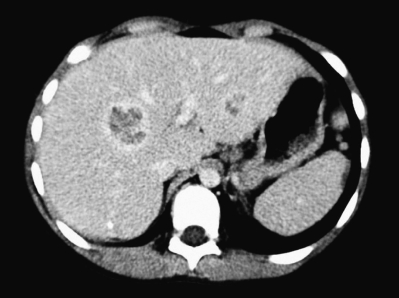

血液所見:赤血球 395 万、Hb 10.5 g/dL、Ht 32 %、白血球 10,200(桿状核好中球19 %、分葉核好中球 43 %、好酸球 4 %、好塩基球 1 %、単球 6 %、リンパ球 27 %)、血小板 46 万。血液生化学所見:総蛋白 7.3 g/dL、アルブミン 3.6 g/dL、総ビリルビン 0.3 mg/dL、AST 28 U/L、ALT 22 U/L、LD 240 U/L(基準 254〜544)、ALP 550 U/L (基準 359〜1,110)、尿素窒素 10 mg/dL、Na 135 mEq/L、K4.5 mEq/L、Cl 102 mEq/L。CRP 11 mg/dL。腹部造影 CTを別に示す。

考えられるのはどれか。

b. 肝膿瘍